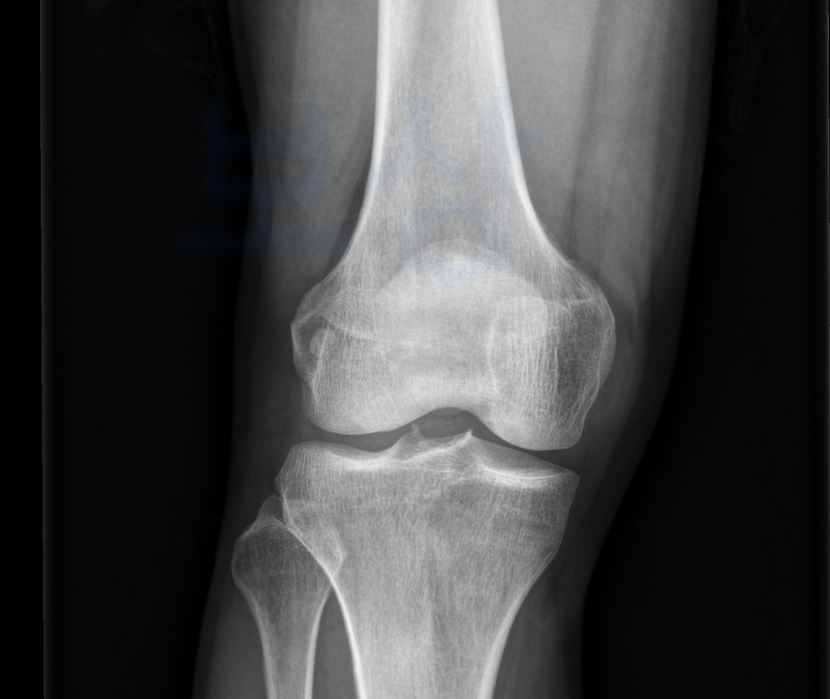

환측 슬관절은 건측 대비하여 7mm의 불안정성이 있었고 손해배상의 맥브라이드 식의 장해 평가 상 전방십자인대 재건술을 받았음에도 수시 보조기가 필요한 상태로서

14.5% 노동능력 상실 판정받았습니다.